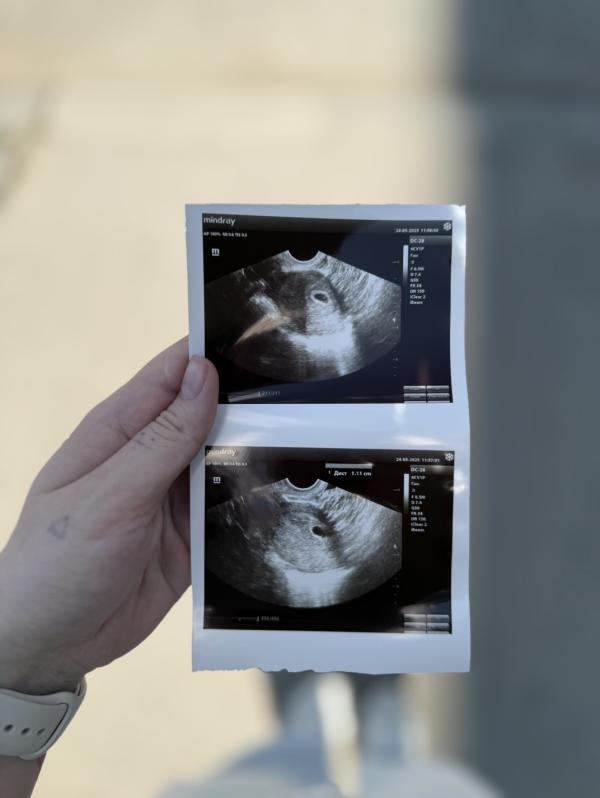

Ну что, сходила на узи

Беременность подтвердилась

Наше первое фото, которое я очень сильно ждала 🥰

24.05.2025